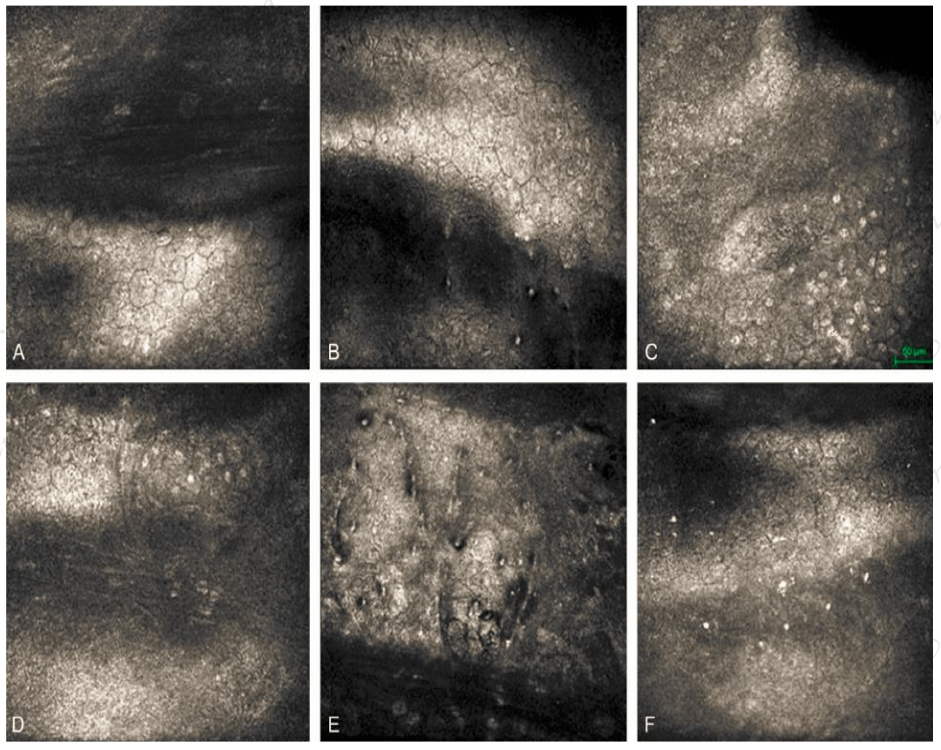

神经系统检查发现kayser-fleischer环(图a),重度构音障碍和发声困难

a: kayser-fleischer ring.